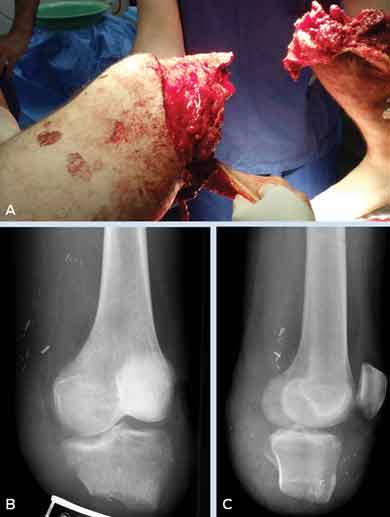

A 23-year-old man was injured while he and his colleagues were riding jet skis after a Christmas party. A colleague collided with him at high speed, crushing his left leg between their jet skis and causing a subtotal amputation just below the knee; only a small bridge of skin remained. The leg was deemed unsalvageable and the amputation was completed in theatre (Box). Several debridements and washouts were performed before the stump was covered with a latissimus dorsi flap. Antibiotic therapy with intravenous meropenem and ciprofloxacin was given for 22 days on the advice of a clinical microbiologist.

The patient will require extensive physiotherapy and occupational therapy during his rehabilitation. He will also need a prosthesis, which will be challenging to develop because of the fastidious nature of the flap and the very short stump (Box).